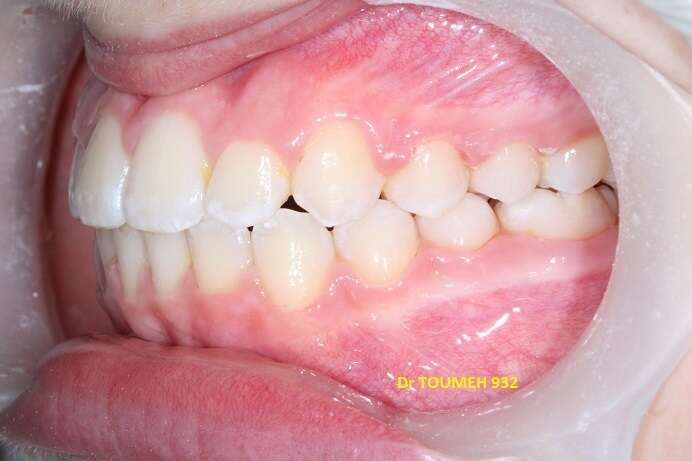

Avant

Après